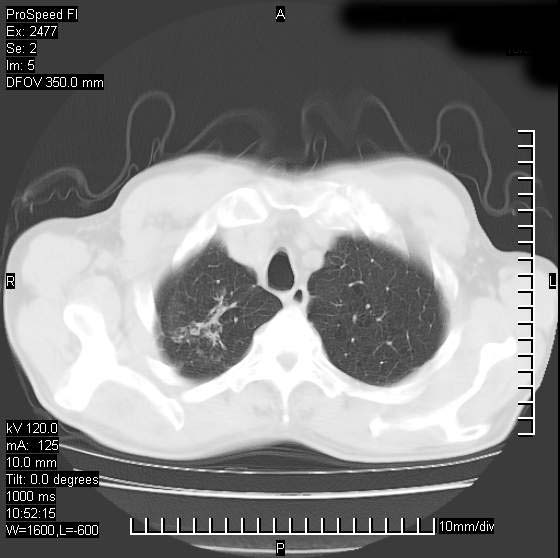

以下是引用天南地北在2007-10-9 14:29:00的发言:[br]1:右上肺结核[br]2:右肺下叶肿块:不支持肺癌,首先考虑炎性病变-肺脓疡可能性大[br]理由:1:临床病史支持,肺脓肿症状不明显应该是不规则服药造成。[br] 2:肿块边缘模糊,周围可见炎性渗出,长毛刺,内见支气管征,不过有点不规则。[br] 我感觉下肺癌这个诊断有点偏左,建议积极抗炎治疗后复查

以下是引用卜一在2007-10-9 15:55:00的发言:[br][br] [br] 1:右上肺结核[br]2:右肺下叶肿块:不支持肺癌,首先考虑炎性病变-肺脓疡可能性大[br]理由:1:临床病史支持,肺脓肿症状不明显应该是不规则服药造成。[br] 2:肿块边缘模糊,周围可见炎性渗出,长毛刺,内见空气支气管征,不过有点不规则。[br] 我感觉下肺癌这个诊断有点偏左,建议积极抗炎治疗后复查![br]支持! [br] [br] [br]

以下是引用wxy7406在2007-10-9 21:02:00的发言:[br]结合临床病史首先考虑感染性病变,但周围型肺癌不能除外,1.患者年龄偏大2.临床有咯血3.(也觉得是最重要的一点)病灶内有偏心性空洞。

以下是引用王仕学在2007-10-9 13:48:00的发言:[br]右下肺周围性肺癌可能性大,最好活检吧

以下是引用hhcckk在2007-10-9 15:18:00的发言:[br]右上肺病灶考虑结核,病灶多种形态并存(纤维化、增殖性病灶并存)[br]右下肺病灶比较难说,个人意见更趋向于“天南地北”的诊断----肺脓肿[br]1、病人有明显的寒战,高热,肿瘤病人很少出现[br]2、病灶周围的肺纹理走向柔和,没有肿瘤病灶常见的集束征[br]3、病灶边缘的毛刺较长,恶性肿瘤多为短毛刺[br]痰中血丝和病人的年龄是两个不利于良性肿块的因素,建议早点活检

以下是引用ydx_74在2007-10-9 15:53:00的发言:[br]右上肺结核,右下中心性肺癌可能大,肺门淋巴结肿大。